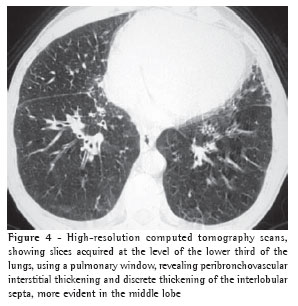

Peribronchovascular interstitial thickening was observed in twelve cases (80%), being bilateral in ten (Figure 4) and unilateral in two (the cases of fibrosing mediastinitis).

Peribronchovascular interstitial thickening was seen in twelve patients (80%). In ten patients, the thickening was bilateral and smooth. In the two cases of fibrosing mediastinitis, the peribronchovascular interstitial thickening was unilateral. Such thickening is identified by determining the thickness of the bronchial walls. The presence of peribronchovascular interstitial thickening reflects, for hydrostatic edema patients, drainage of the fluid via central interstitial pathways.(3) Em outro estudo,(9) o espessamento foi achado na tomografia computadorizada de alta resolução em quatro de sete pacientes.

In another study,(9) such thickening was detected in the high-resolution computed tomography scans in four of seven patients.